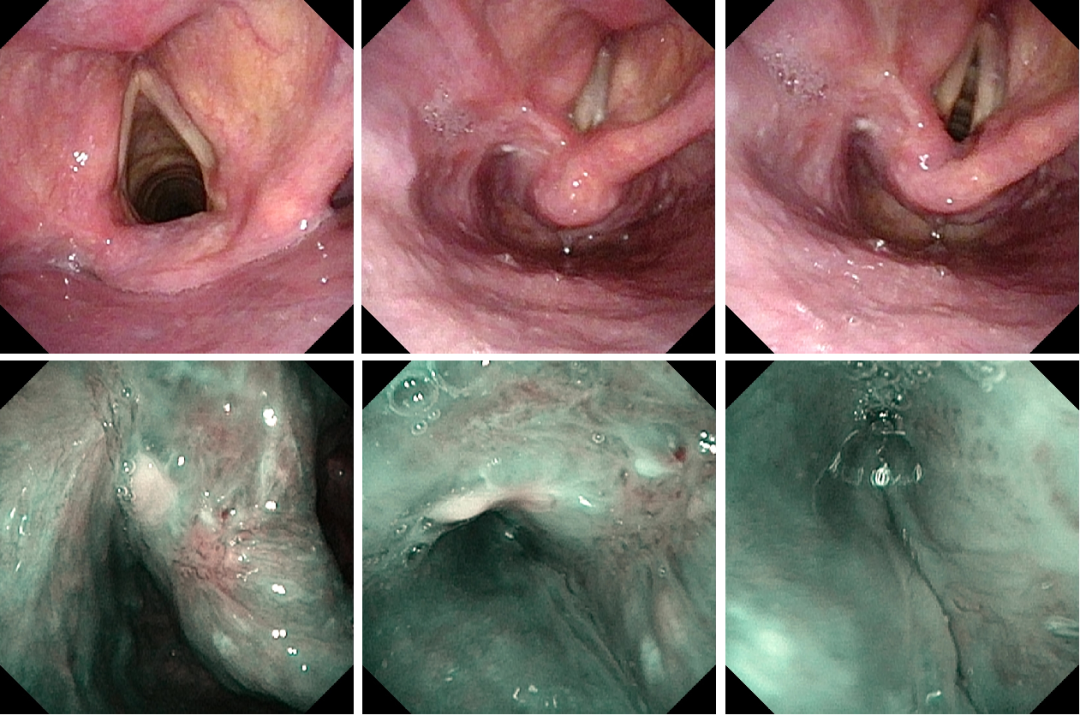

图片

术后一年复查

1、术前评估病变范围尤为关键。可借助高清电子喉镜、NBI内镜及增强CT对病变范围进行详细评估,全面了解病变的粘膜范围及粘膜下的侵及深度,为术中切除深度提供预判。

2、选择合适型号的支撑喉镜对病变进行暴露是保证病变完整切除的关键,术中需根据病变范围变换支撑喉镜位置,保证安全边界的清晰暴露。

3、微创手术依然必须遵循肿瘤切除的“one- block”原则来进行。对恶性肿瘤患者来讲,高生存率是主要的治疗目标,在此基础上才可追求功能的保全。

4、CO2激光具有良好而精准的切割效果,应用于能够充分暴露病变的下咽恶性肿瘤的微创治疗,术后瘢痕轻微,是有益的治疗方式。术中需注意辨别解剖层次及毗邻,注意重要结构的保护。